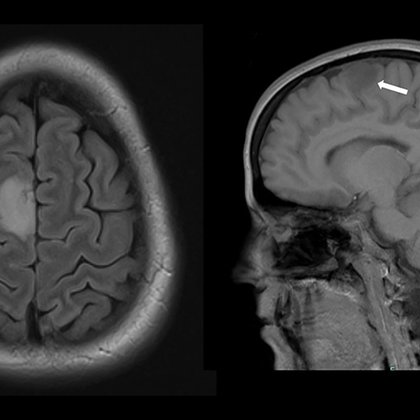

RP experiences #seizure when listening to songs between 80 and 100 bpm. H Kelly, MD, T Gregory, MD @timgregorymd, & J Graber, MD @dr_graber report on a case of #musicogenic #epilepsy & #glioma. @MDAndersonNews @UWNeurology @MadiganHealth @AmEpilepsySoc https://t.co/z31PgHcLTc

Glioma and glioblastoma may sound alike, but they are different types of brain tumors. Here, our Dr. Ashley Aaroe shares how they are diagnosed and how that distinction impacts treatment. https://t.co/t3fcGPEzB9 @AshleyAaroe #glioma #glioblastoma #EndCancer

Glioma and glioblastoma have similar names. And while glioblastoma is a type of glioma, it's not treated the same way as all other gliomas. Ashley Aaroe, M.D., explains the differences between these...